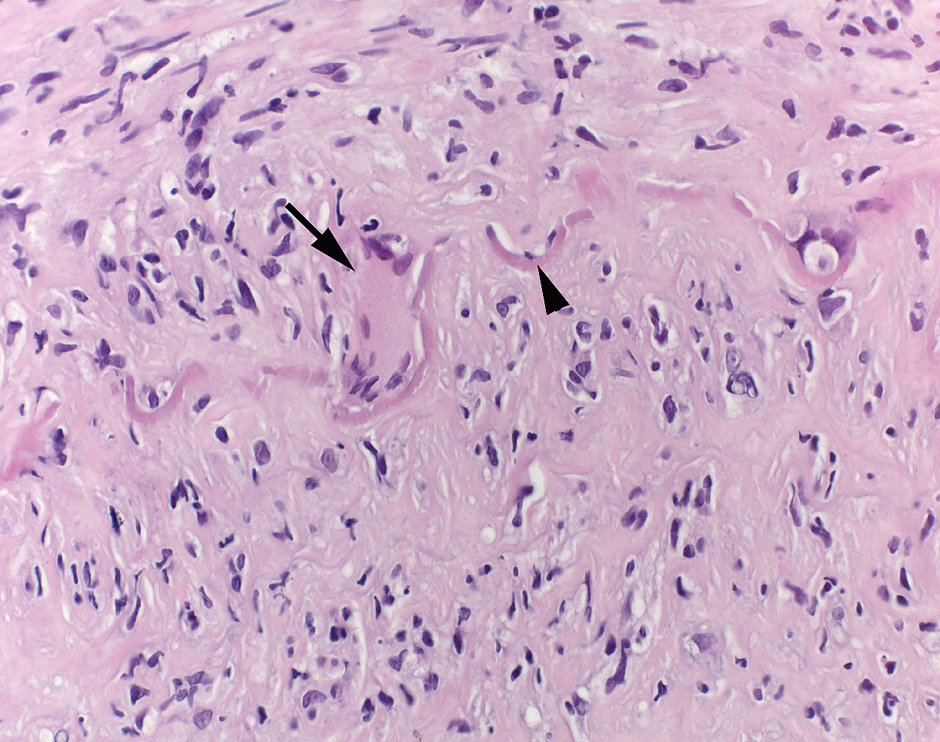

Giant cell arteriitis (GCA) affects large and medium sized arteries and is the most prevalent of the systemic vasculitis syndromes [1, 2]. Inflammation of the vessel wall is characterised by infiltration of T-cells and macrophages, presence of eponymous giant cells, granulomatous lesions, intimal hyperplasia and destruction of elastic fibres (fig. 1) [3].

Figure 1

Histopathology picture from a GCA-patient. Temporal artery biopsy with characteristic histological findings of active giant cell arteriitis: The arterial wall shows a dense chronic lymphohistiocytic inflammatory infiltrate. A multinucleated giant cell (arrow) lies next to the disrupted elastic lamina (arrowhead). The intima in the lower half of the image is thickened. H&E, 400x